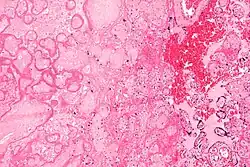

Micrograph of a placental infarct. H&E stain. | |

A placental infarction results from the interruption of blood supply to a part of the placenta, causing its cells to die.

Small placental infarcts, especially at the edge of the placental disc, are considered to be normal at term. Large placental infarcts are associated with vascular abnormalities, e.g. hypertrophic decidual vasculopathy, as seen in hypertension.[1] Very large infarcts lead to placental insufficiency and may result in fetal death. Placental infarcts are generally detected after birth, although using ultrasound may be a way to notice infarcts prenatally. This method still needs more research and may not be completely effective in noticing infarcts. [2]

Maternal floor infarcts are not considered to be true placental infarcts, as they result from deposition of fibrin around the chorionic villi, i.e. perivillous fibrin deposition.